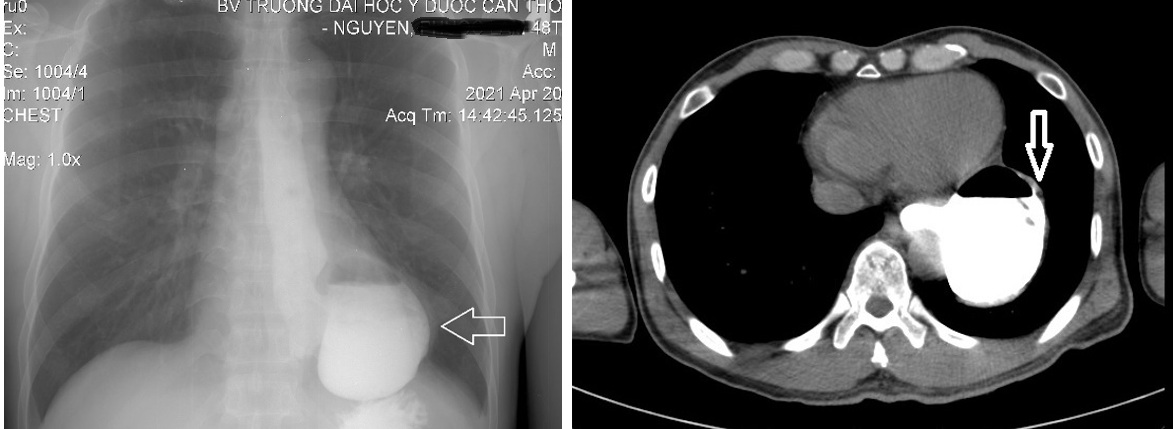

Bệnh nhân được chỉ định phẫu thuật nội soi cắt túi thừa thực quản kèm điều trị trào ngược dạ dày thực quản. Phương pháp vô cảm: Mê nội khí quản. Tiến hành cắt túi thừa, chống trào ngược bằng phương pháp Dor. Phẫu tích cắt dọc tới cổ túi chỗ nối thực quản dạ dày có động mạch đường kính khoảng 3mm chạy ngang đè vào ống niêm mạc ngang vùng cổ túi thừa, xử trí cắt động mạch. Thời gian cuộc mổ khoảng 4 giờ, lượng máu mất khoảng 20ml. Không ghi nhận tai biến trong lúc mổ.

Hình 2: Túi thừa thực quản được cắt bằng Echelon 60 ngang cổ túi